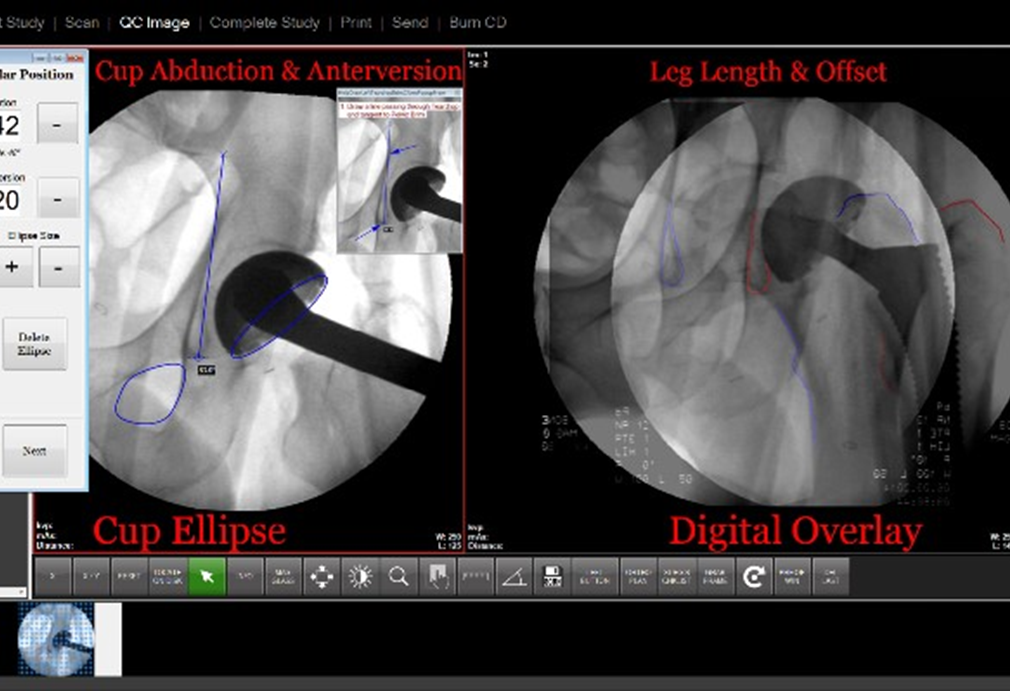

Anterior Hip Replacement

•C-Arm enters on opposite side of hip of interest

•At RH: images of the affected hip and pelvis are taken to see the trochanters and obturators

•PA views only

•Radlink may be used depending on physician

•There is a cable that connects the C-Arm to the Radlink tower so that the rep can pull images from the c-arm

Radlink at RH

•Radlink software allows a live image to be grabbed from the C-Arm or portable monitor and shown on the Radlink monitor.

• The doctor or equipment rep can perform different manipulations to the image on the Radlink monitor.

•Examples: road mapping, sizing

•Always ordered as No Dictation with Radlink order

•Dr. Slotkin, Dr. Longenecker, and Dr. McAlpine are the doctors who may use this equipment